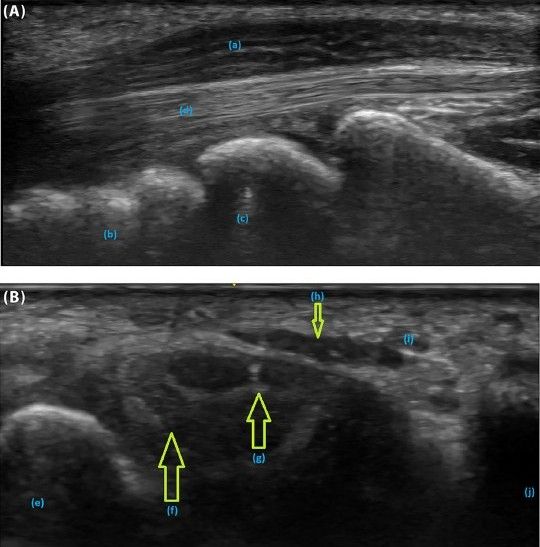

onlinelibrary.wiley.com/doi/epdf/10....

#neuroimaging #neurology #neuroskyence #radiology #carpaltunnel #ultrasound

onlinelibrary.wiley.com/doi/epdf/10....

#neuroimaging #neurology #neuroskyence #radiology #carpaltunnel #ultrasound